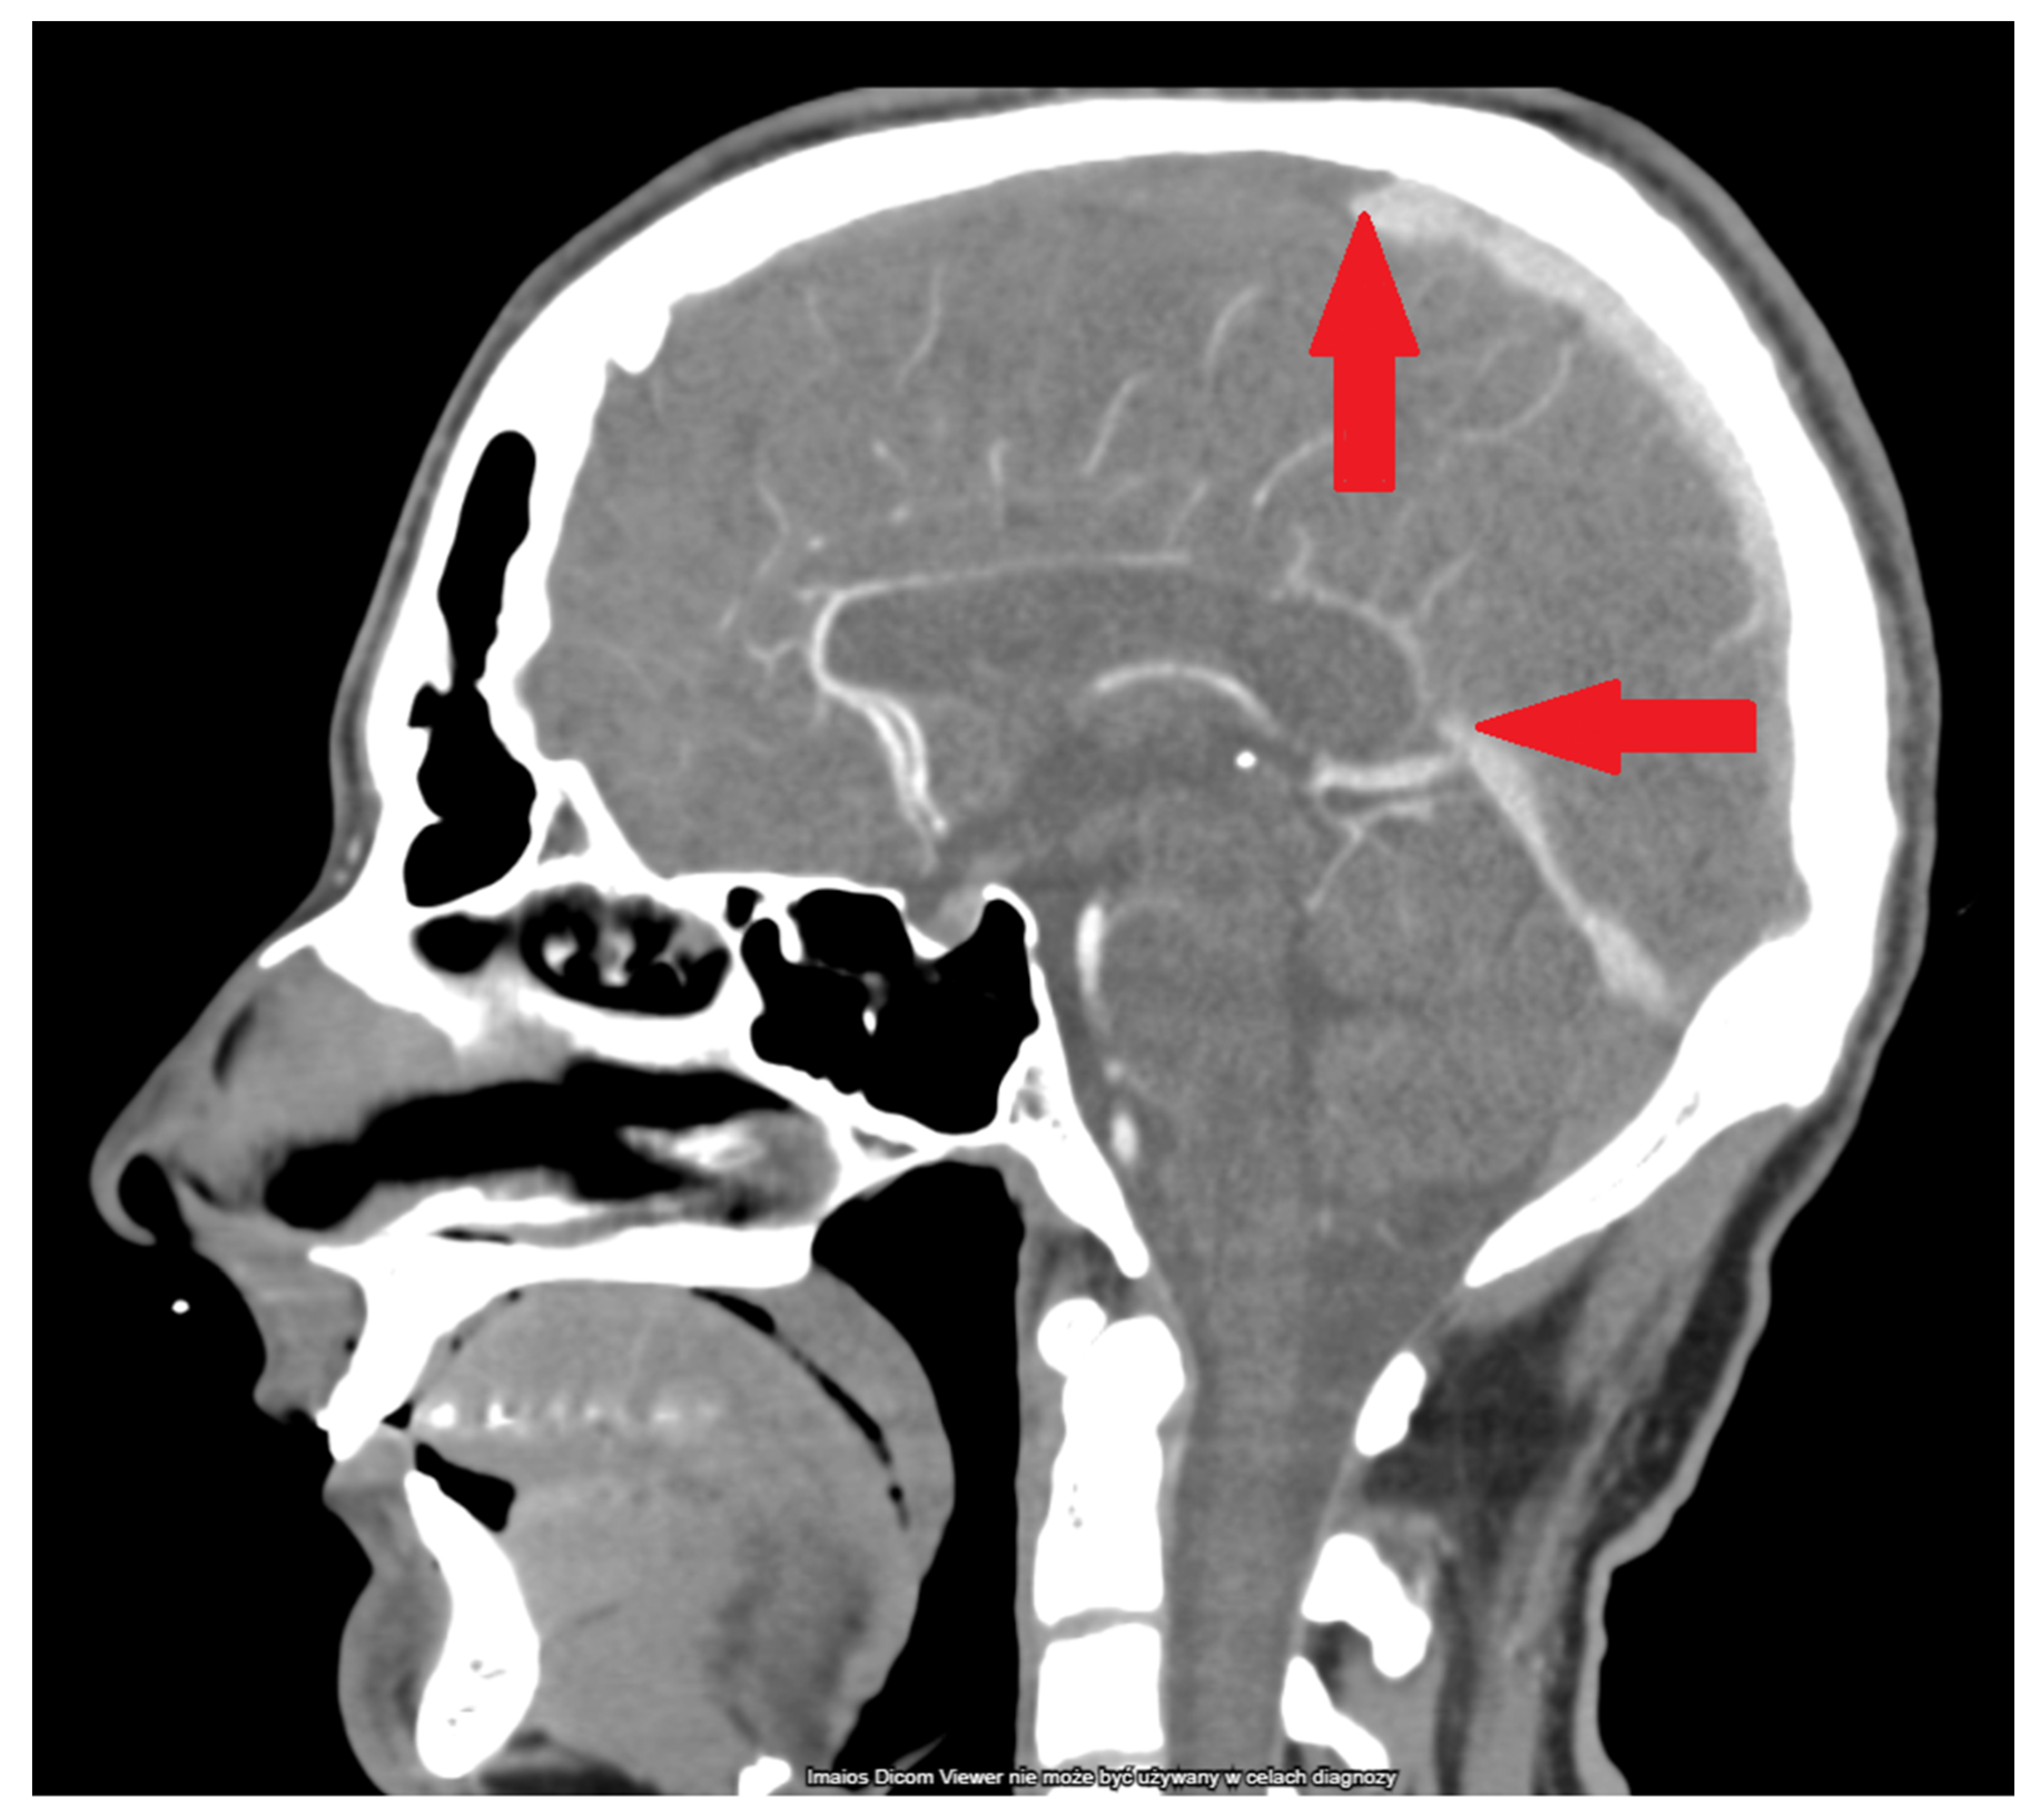

3.5. Imaging Studies